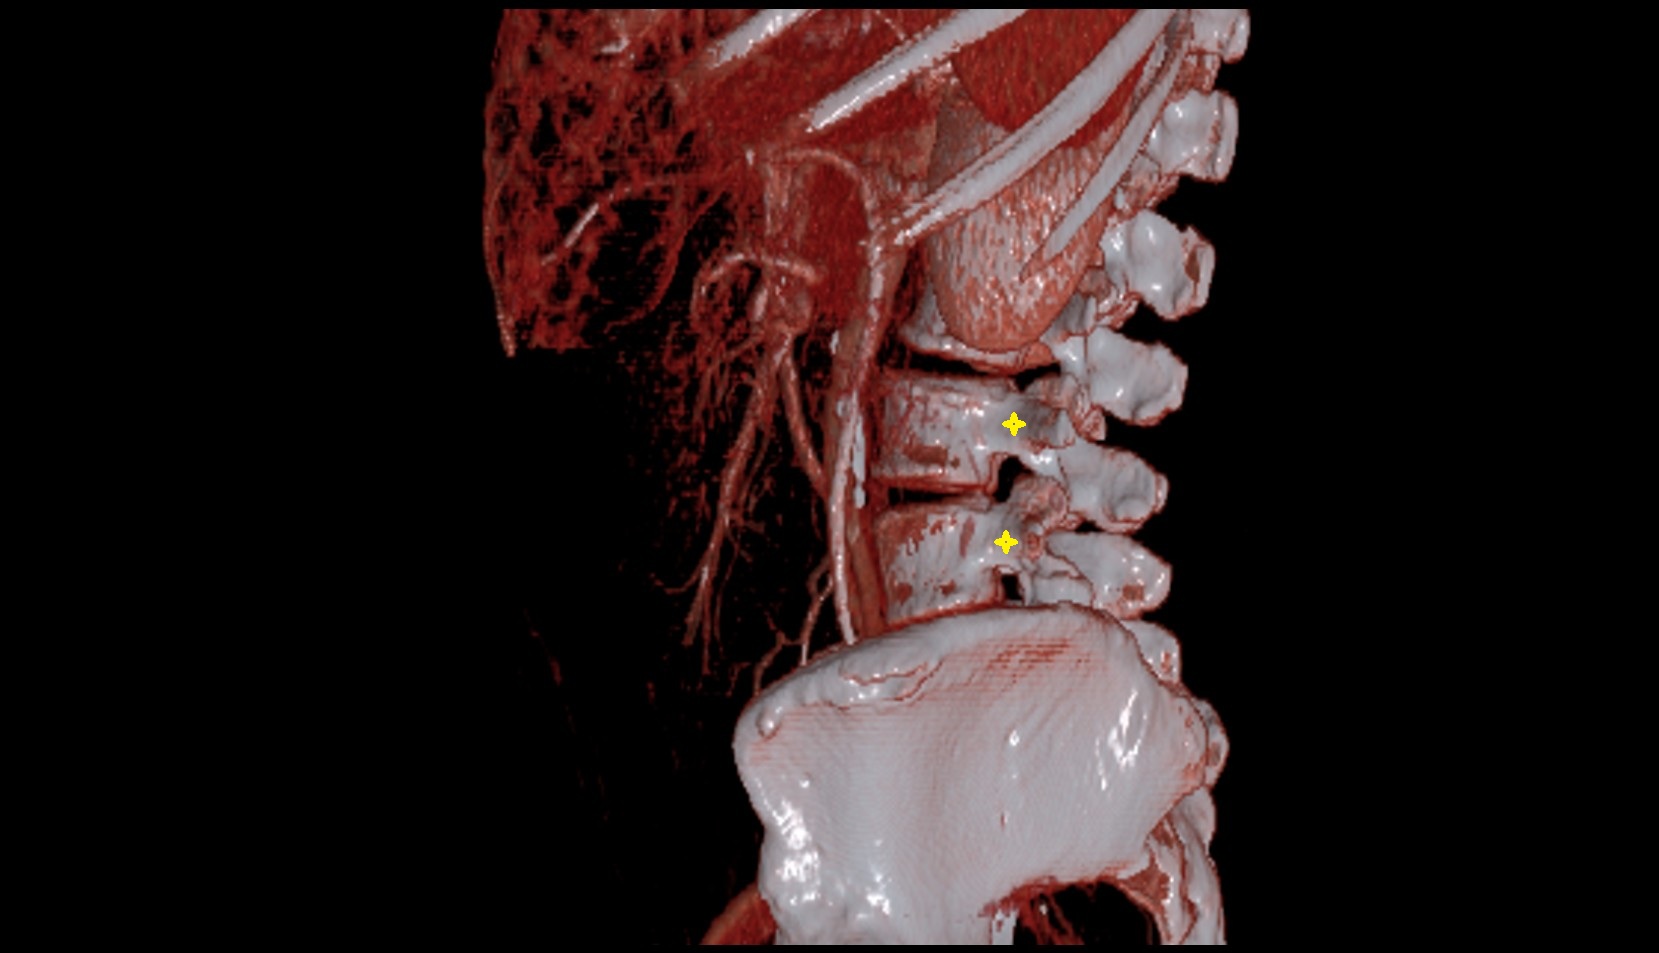

- L4–L5 Intervertebral Disc

- L3–L4 Intervertebral Disc